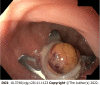

Rectal neuroendocrine neoplasms (r-NENs) are considered among the most frequent digestive NENs, together with small bowel NENs. Their incidence has increased over the past few years, and this is probably due to the widespread use of endoscopic screening for colorectal cancer and the advanced endoscopic procedures available nowadays. According to the current European Neuroendocrine Tumor Society (ENETS) guidelines, well-differentiated r-NENs smaller than 10 mm should be endoscopically removed in view of their low risk of local and distant invasion. R-NENs larger than 20 mm are candidates for surgical resection because of their high risk of distant spreading and the involvement of the muscularis propria. There is an area of uncertainty regarding tumors between 10 and 20 mm, in which the metastatic risk is intermediate and the endoscopic treatment can be challenging. Once removed, the indications for surveillance are scarce and poorly codified by international guidelines, therefore in this paper, a possible algorithm is proposed.